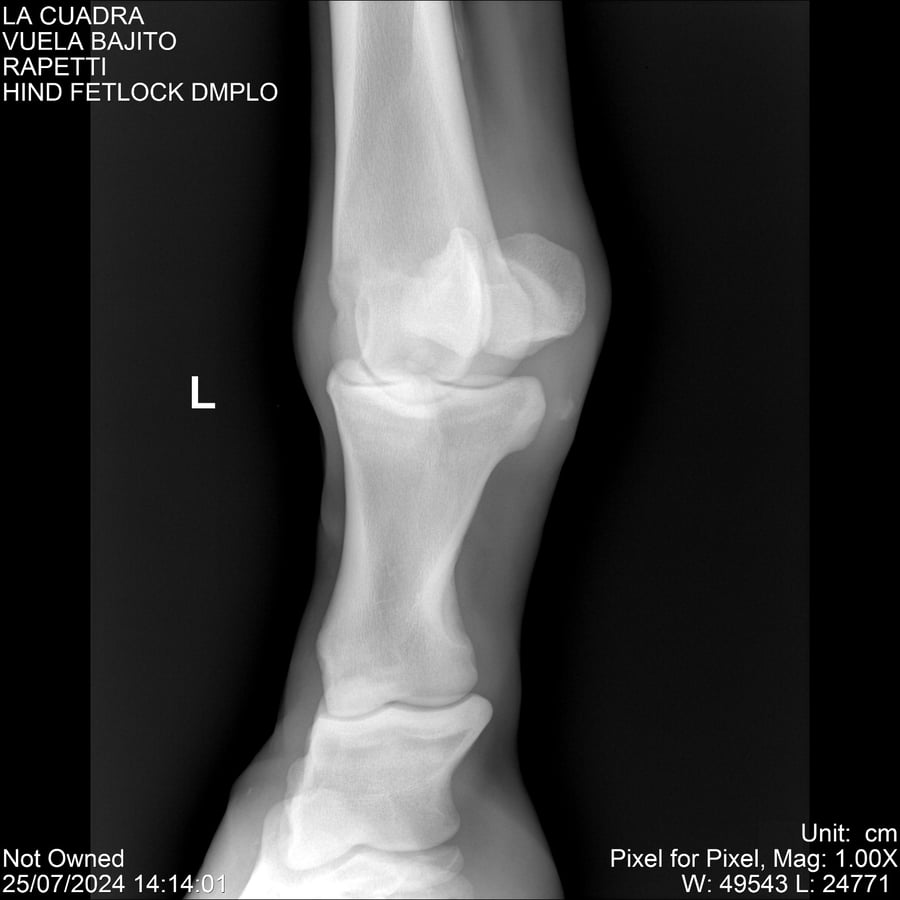

LOTE 16, VUELA BAJITO Lote Anterior Volver al remate Lote Siguiente Ficha Contacto Montevideo - Ficha del Lote Identificador: #284451 Categoría: Yeguarizos Montevideo - 77 Visualizaciones ClicData Contacto Empresa: Abelenda N. R., Walter Hugo Nombre*: Teléfono* : E-mail* : Mensaje Enviar Registrese gratis Este contenido Exclusivo está disponible sólo para usuarios registrados Ingresar